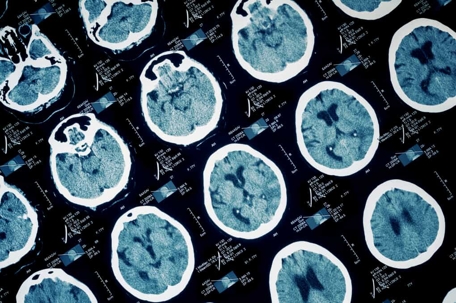

Close up of brain scan imaging

Traumatic brain injury (TBI) is an increasingly common condition that can lead to serious and long-lasting neurological, cognitive, and physical challenges. A new report from the National Academies of Sciences, Engineering, and Medicine calls for the current TBI categories to be updated in order to provide better guidance for patient care.